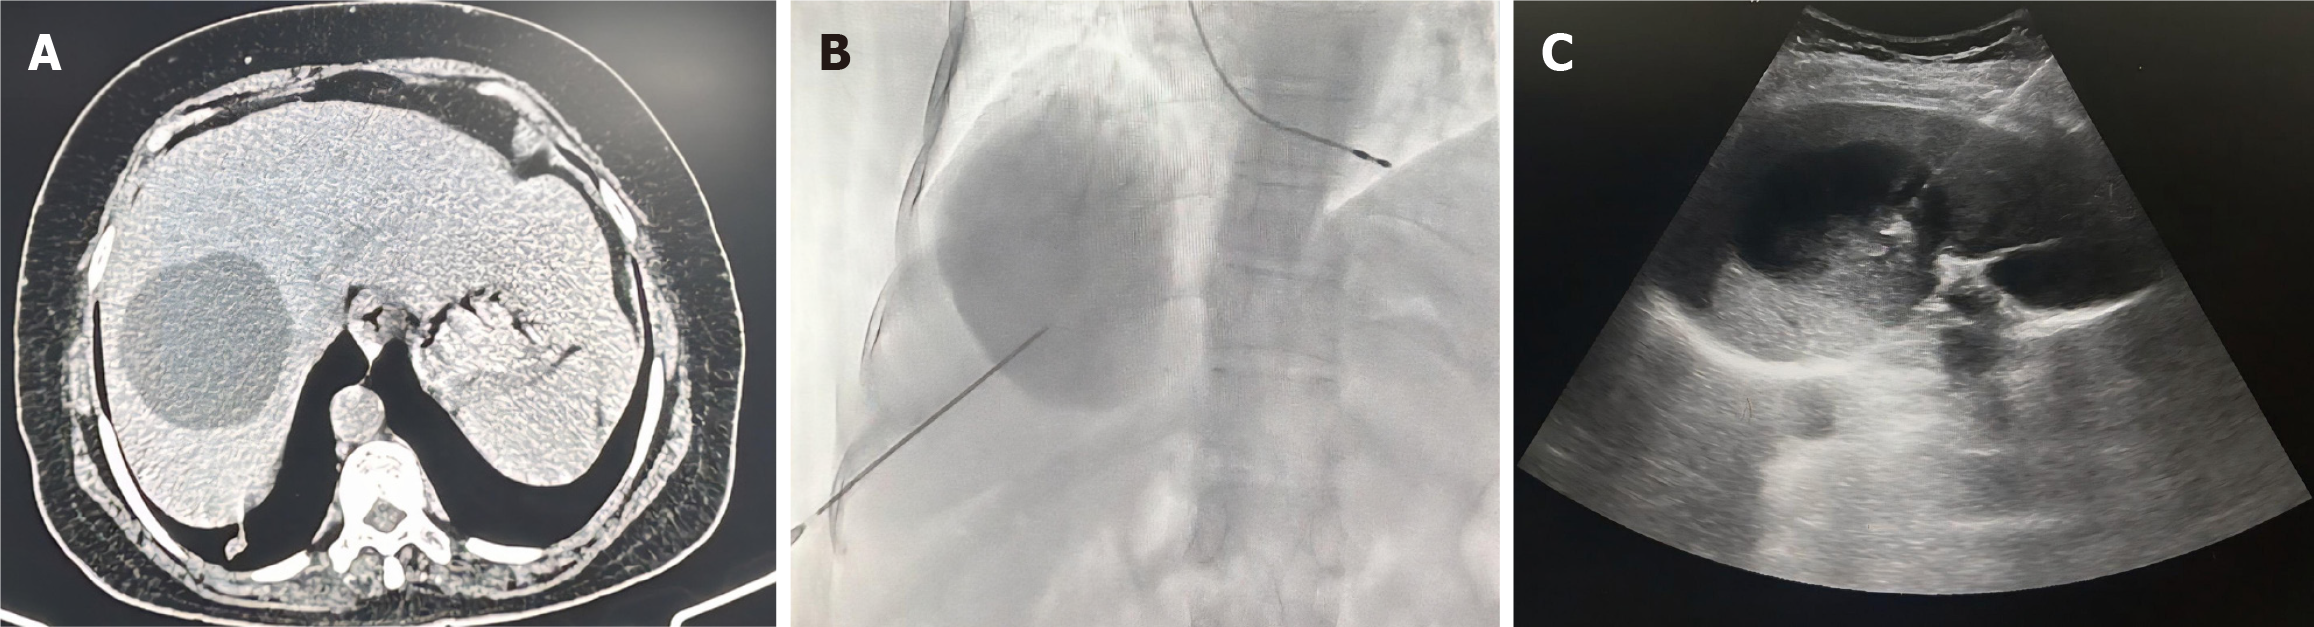

Örmeci technique

This technique is a modification of the PAIR technique, and can be employed for CE1, CE2, CE3a, and CE3b HHC (Figure 8)[45]. The first step is puncture of the HHC using a 22-G needle, which is in contrast to the 18G needle used in PAIR, leading to a reduced risk of cyst fluid leakage and secondary peritoneal hydatidosis[45]. Multiple punctures can be performed in the same session (up to 5), especially for CE2 and CE3b cysts, to achieve better distribution of the sclerosing agent. The volume of fluid aspirated is 3 times the largest dimension of the HHC (3 cm3 for every 1 cm), which equates to ≤ 2 % of the total cyst volume[45]. This is much less than the 20% fluid aspirated in PAIR. Because of this, there is less reduction of the intracystic pressure, which may not fall below the normal intrabiliary pressure, thereby reducing the chances of development of cysto-biliary communication. The next step is injection via the puncture needle of equal volume of the aspirated fluid with 95% ethanol (2/3 volume) and 1% polidocanol (1/3 volume), which is kept in situ for 5 minutes. The advantage of polidocanol is that it enhances the sclerosing effect of ethanol, and it obstructs small communications with the biliary and venous system, if present. Catheters are not used, which reduces the chances of infection and shortens hospital stay. The scolicidal agent is not re-aspirated, which increases the scolicidal effect. Very limited evidence, largely derived from small case series and observational studies, suggests that the Örmeci technique may be associated with higher clinical success and lower morbidity, mortality, and recurrence rates compared with PAIR[46]. However, these findings are preliminary, and larger studies are required to validate their efficacy and safety.

Figure 8

Figure 8 Örmeci technique. A: Axial computed tomography image shows a hydatid cyst in the right lobe of the liver; B: Fluoroscopic spot image during Örmeci procedure: Contrast is injected through the puncture needle, which fills the cyst cavity with no opacification of biliary radicles, ruling out cysto-biliary communication; C: Ultrasound image depicting puncture needle in situ within the hydatid cyst.